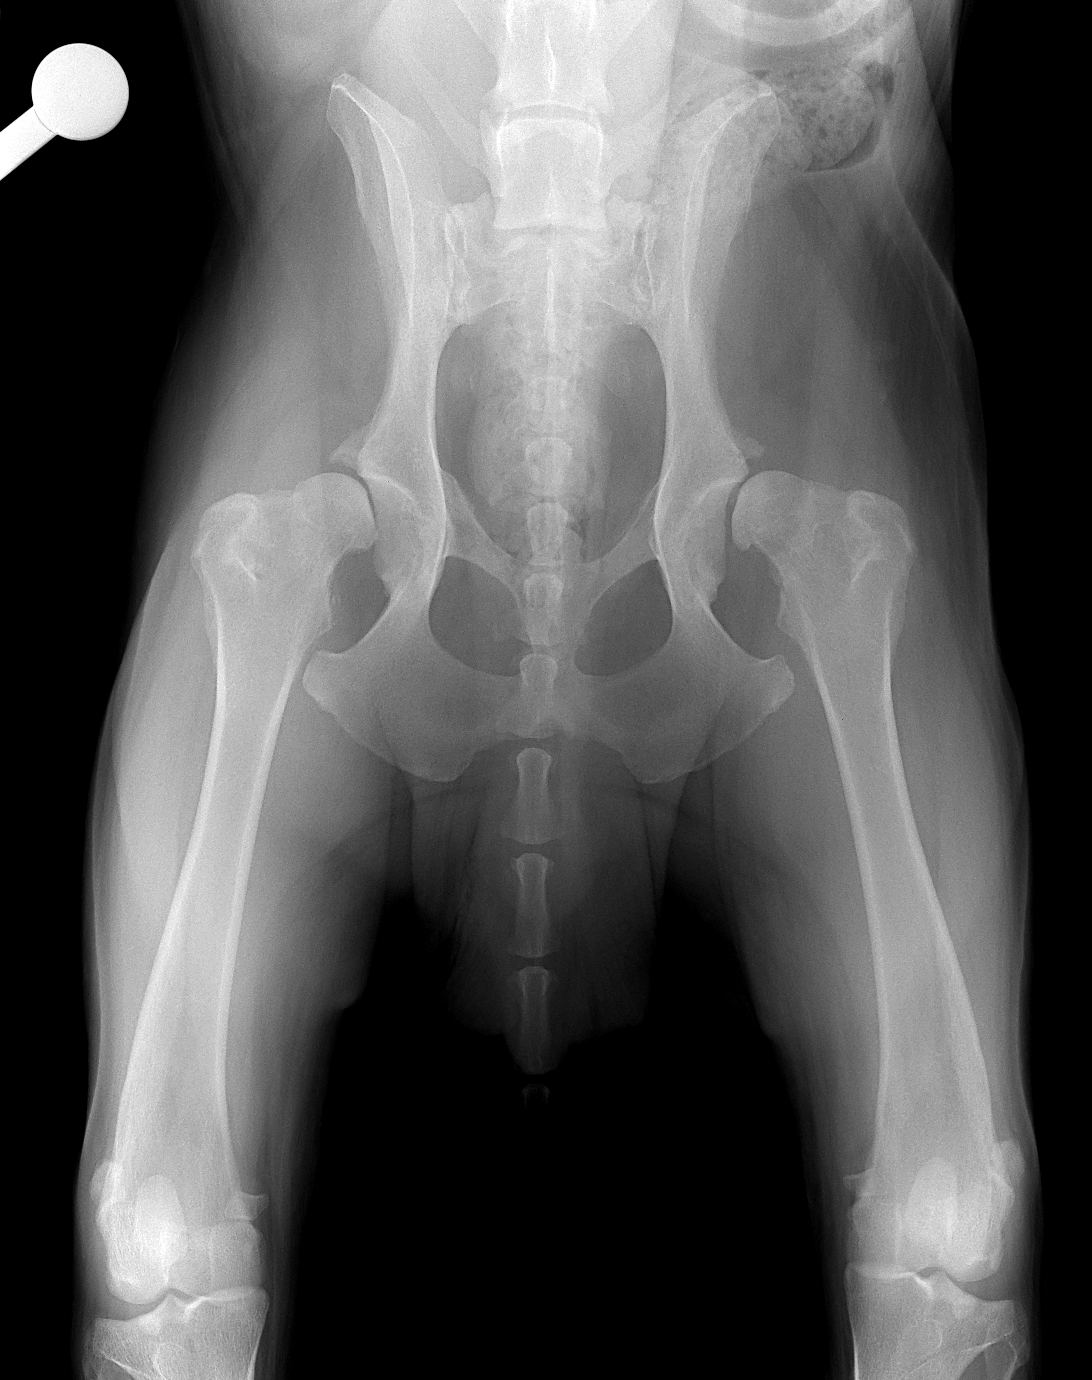

45kgの大型犬が股関節形成不全による痛みがあるとの事。他県より紹介来院されました。KyonのTHRシステム(人工関節)で傷んだ関節を置換しました。関節炎による痛みを感じるのは人も動物も同じです。出来るだけ痛みのない生活を過ごしてもらいたいと思います。インプラントはCup AOL 42° Large STEM 17°、Head19mm、Neck S、29.5 、Cup Anteversion 30°で埋入されています。内科治療に反応のない骨関節炎には人工関節で対応する事も可能です。しばらくは安静が必要です。